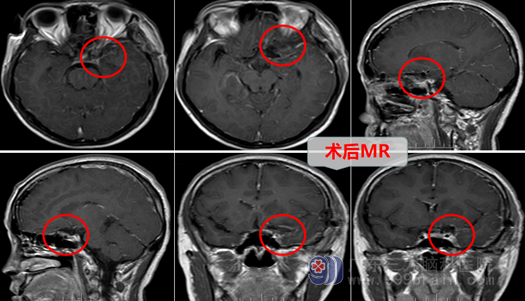

2022年6月28日欧阳辉教授团队为曾姐进行了“左侧内侧型蝶骨嵴脑膜瘤切除术”,术中:医生在高清智能显微镜的帮助下,认真仔细操作,雕刻式分离、切除肿瘤,妥善保护神经血管,结果:完全切除了肿瘤,且并未损伤正常组织结构。术后:曾姐神志清醒,回答正确,四肢活动都是很好的,恢复几天后,再也没有出现像手术前那样的头颈痛等不舒服的症状。

曾姐及其家人对手术效果非常满意,看着曾姐的身体一天天的恢复得越来越好,她们对外十科医护人员表示非常感谢!